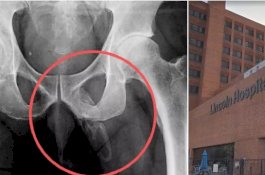

Alat Vital Pria Ini Berubah Jadi Tulang karena Kondisi Medis yang Langka